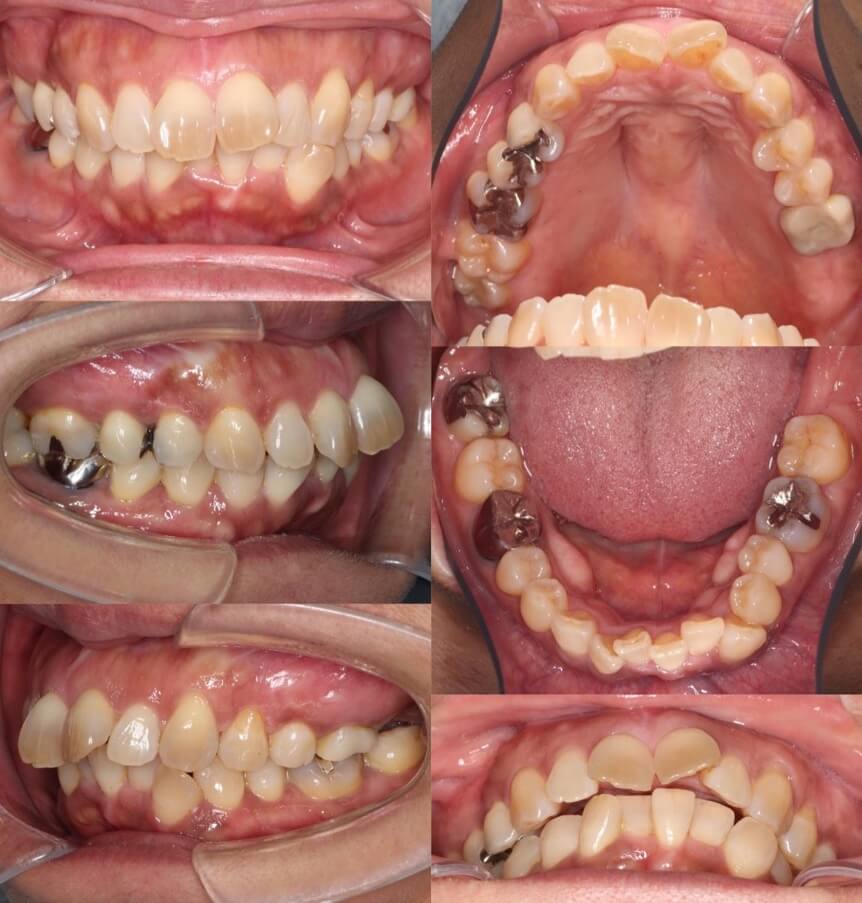

43歳女性・唇側矯正装置・抜歯

<症例概要>

主訴:前歯のがたつきと・かみ合わせ

年齢・性別:43歳女性

住まい:千葉県佐倉い市

症状:叢生・前歯交叉咬合・左上5番萌出不全

治療方針:右上下4番・左上下5番(計4本)

治療装置:唇側矯正装置

固定装置:リンガルアーチ

治療期間:2年6か月

リテーナー:下フィックス+上下クリアタイプ

治療費用:968,000(税込)

代表的副作用:痛み・治療後の後戻り・歯根吸収・歯髄壊死・歯肉退縮

▶︎その他の副作用

抜歯矯正ではふつう4番を抜歯するのですが、歯の状況によっては5番を抜歯することもあります。左上の5番の歯が半分弱しか出てきてないことと、左下の5番が大きく外側に転位していることから、左側のみ5番を抜歯し矯正治療を行いました。やや歯列の正中線は、4番を抜歯した右側に引っ張られたのですが、患者さんはそこまで気にしていませんでした。